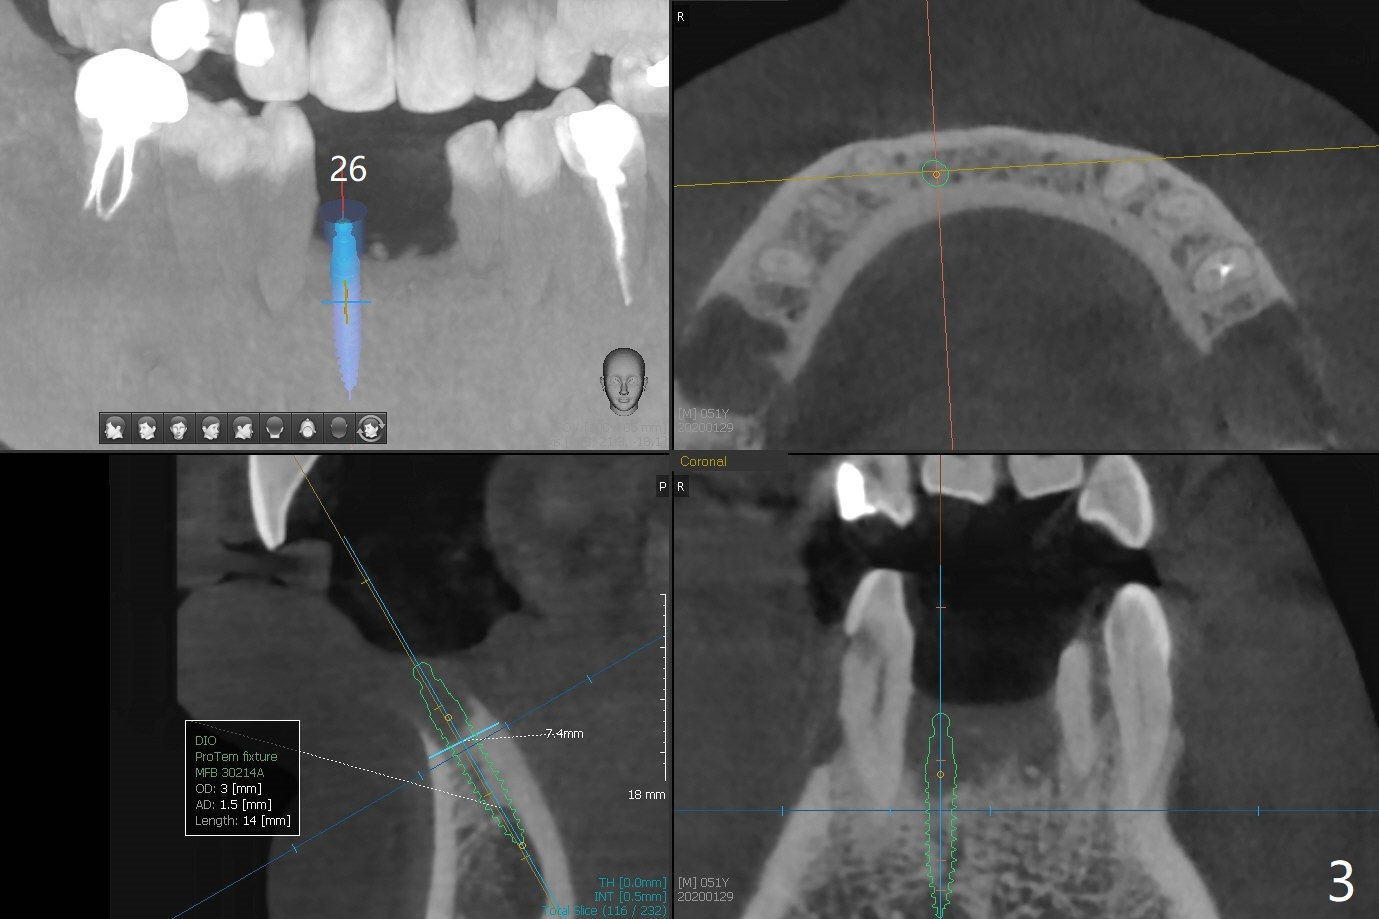

A 51-year-old man with chronic periodontitis requests implants at 19, 24-26 and 30 nearly 2 months post extraction without bone graft (Fig.1). He is willing to quit smoking by using electronic smoke. After SRP, the tooth #6 with supragingival fracture will be saved by post and crown. The mesiodistal space seems to be too narrow for implant (Fig.2). 1-piece implants will be placed at #24 and 26 for FPD (Fig.3,4). Implant placement at #19 and 30 will involve incision, socket redebridement, guide, bone graft (sticky bone), PRF membranes as a barrier and sutures (Fig.5,6).